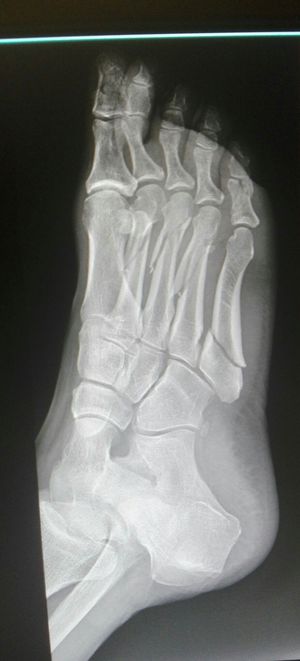

Xray

Fractures

Metatarsus

Multiple # 2,3,4 MT head to shaft displace +,5th base#

Rx ORIF